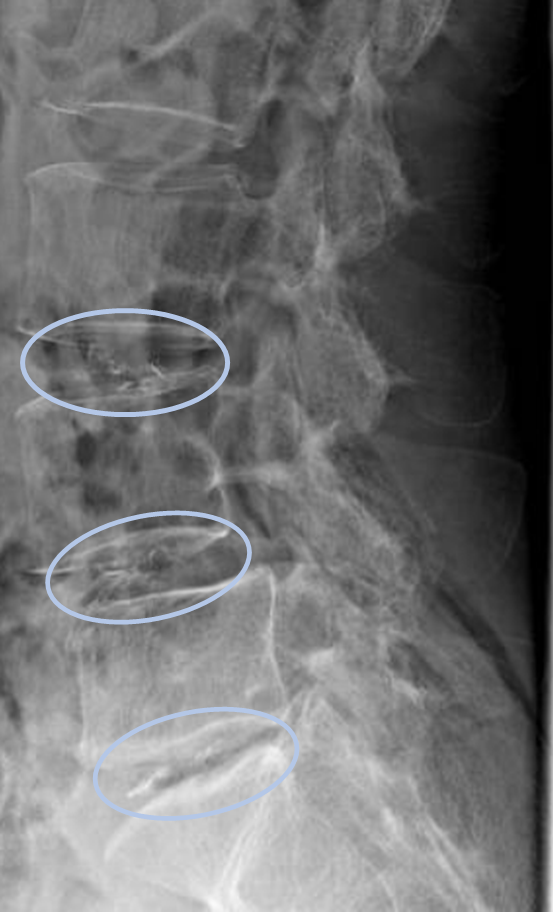

画像及び所見について

- L3/4,4/5,5/s-椎間板変性

- L5-後方滑り

以上の事が画像上認められます。

・L3/4,4/5,5/s-椎間板変性を認め、主症状の原因の可能性が高い。